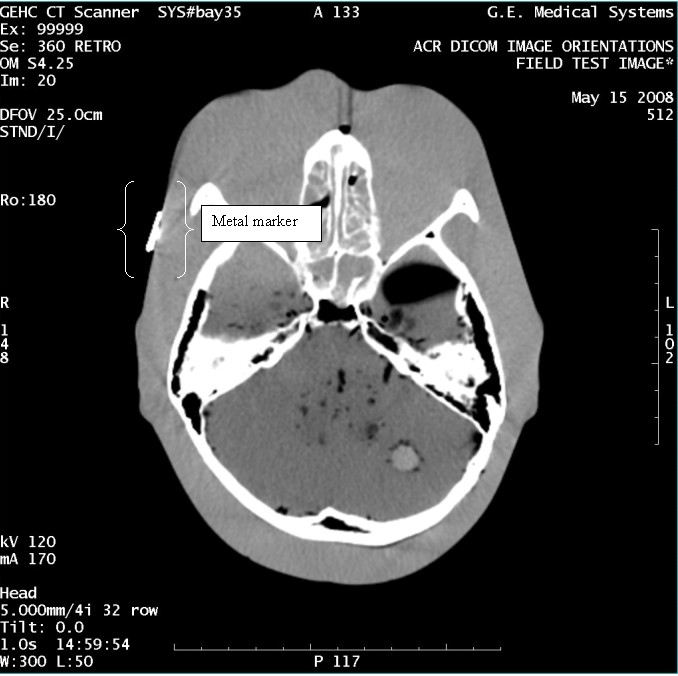

- With the support of the site personnel, examine the images sent

to the Review Station (i.e., 12 series, each with 1 image) and compare

their orientation to the images in this document.

- Each image contains a metal marker on the phantom's right cheek.

- Each image in this document contains a description of the expected

orientation of the metal marker (i.e. to prove Left and Right) as

well as the Posterior and Anterior orientation description.note:

The sample images included in this document use “R”, “L”, “P”, and “A” for “Right”, “Left”, “Posterior” and “Anterior” orientation. The Hospital Review Station may use a different style of annotation. The style used is not relevant to this procedure.

- Each image in this document has sufficient space to store the observed results for up to 4 Review Stations.

- Enter ‘Y’ in the space to indicate the observed result matches the expected.

- Enter ‘N’ in the space to indicate the observed result does not match the expected.

- Enter “NA” in the space if a column is not being used.

- Repeat for each destination.

Figure 13. Exam 99999, Series 360